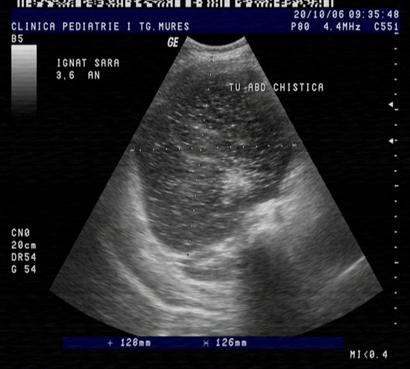

Fig. nr. 268. Formatiune anecogena abdominala fetala independenta de rinichi, la 28 sapt,ulterior in crestere la copilul de 3 ani

Fig. nr. 269. La peste 3 ani de la diagnosticul intrauterin, formatiunea tumorala abdominala ajunge la dimensiunea de 12 cm diametru si cu o structura inomogena cu mici hiperecogenitati sugestive ptr un teratom